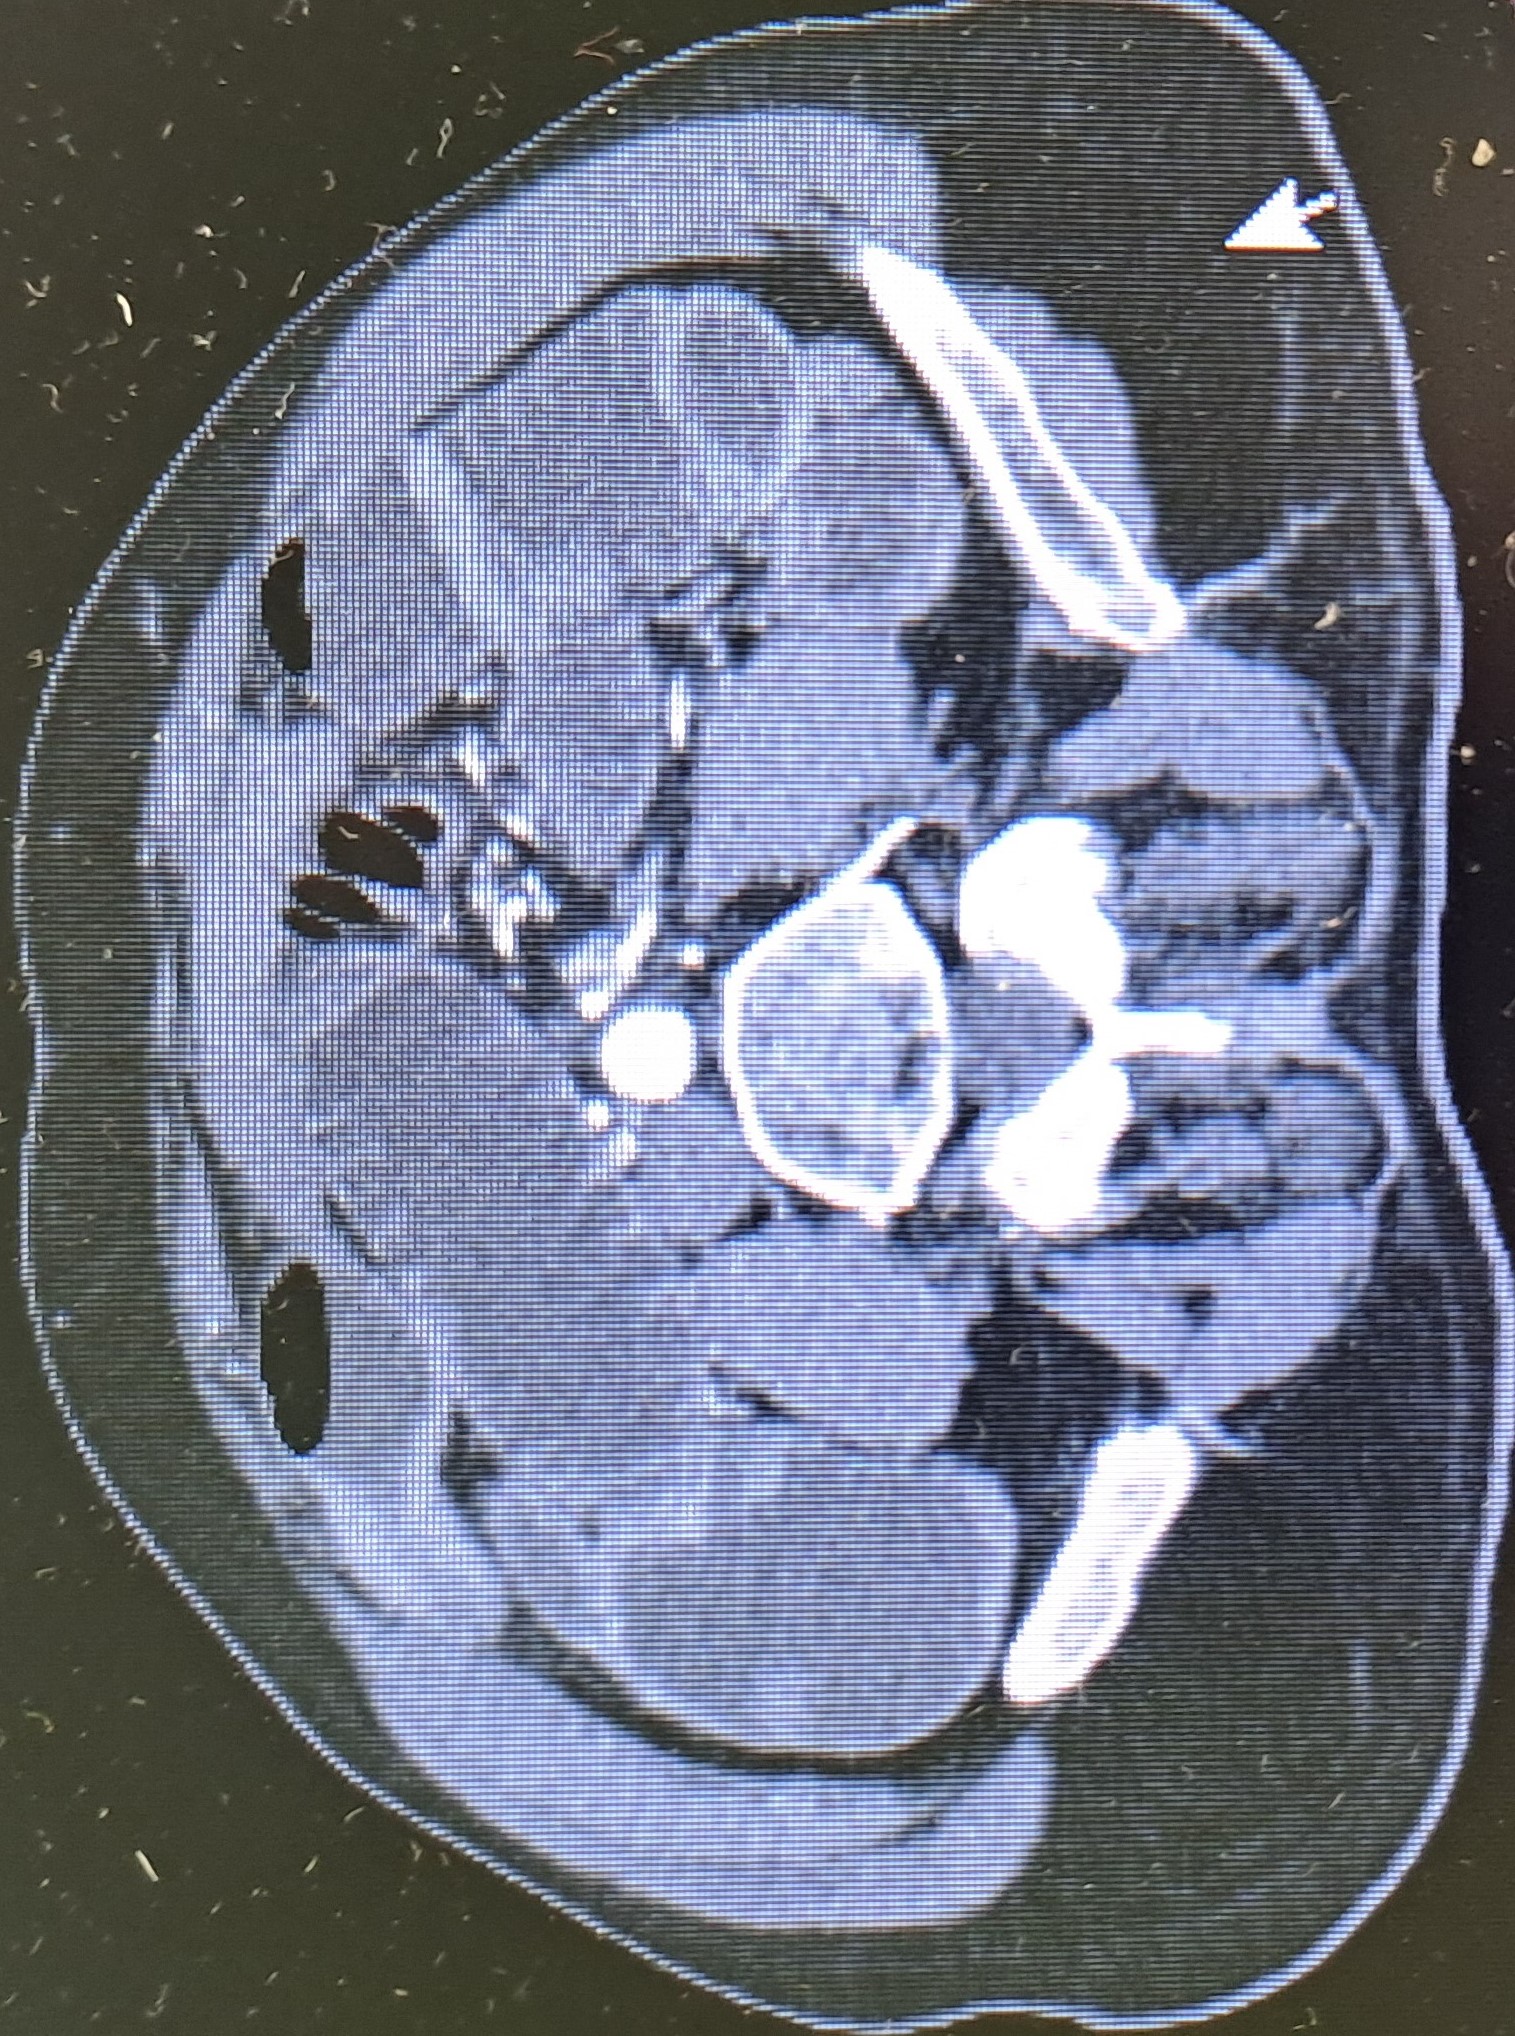

TAC abdominopélvico: Cambios radiográficos sugestivos de apendicitis aguda con íleo asociado.

Apendicitis aguda con íleo paralítico asociado e insuficiencia renal aguda.